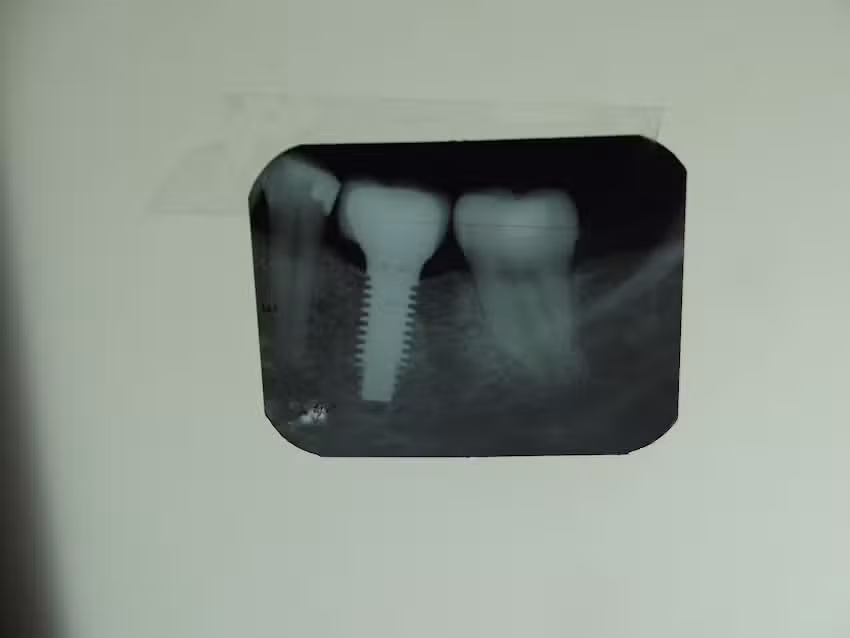

En este consultorio, la atención se orienta a la salud dental integral, con énfasis en tratamientos clínicos básicos y resolutivos más que en propuestas de estética avanzada o servicios de gran volumen. El profesional figura en distintos directorios médicos como especialista en odontología general, lo que incluye procedimientos habituales como obturaciones, limpiezas, controles preventivos y tratamiento de piezas en mal estado. A su vez, algunos listados lo vinculan con prácticas de periodoncia e implantes, aunque no se promociona como un gran centro de alta complejidad, sino como un consultorio particular que da respuesta personalizada a cada paciente.

El enfoque está puesto en la resolución integral de los problemas más frecuentes de salud bucal: caries, dolores localizados, piezas en mal estado y necesidad de tratamientos de restauración. Algunos listados lo señalan también como vinculado a la periodoncia y a los implantes, lo que sugiere que puede abordar tratamientos más avanzados, siempre dentro del marco de un consultorio particular. Para el paciente, esto se traduce en un servicio que combina la experiencia de un profesional con años de ejercicio con la atención directa, sin intermediarios.